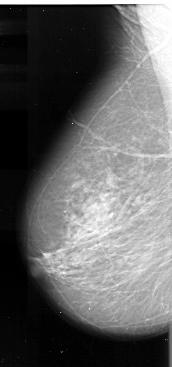

A_1081_1.LEFT_CC

LEFT_CC LINES 6331 PIXELS_PER_LINE 3406 BITS_PER_PIXEL 16 RESOLUTION 42 NON_OVERLAY